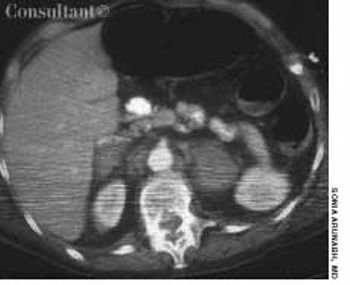

A 23-year-old woman presents withweight loss, epigastric pain, abdominalfullness, and mild nausea. Shereports that she has had a slow-growingmass on her upper middle abdomen.She denies vomiting and doesnot have evidence of jaundice. Theonly significant finding in her medicalhistory is a myringotomy performedmany years earlier. She currentlytakes an oral contraceptive.